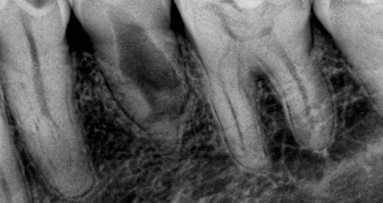

A nivel clínico, el Dr. Norbert Puello impartió una conferencia titulada "Planeamiento en prótesis sobre implantes", en la que mostró casos clínicos utilizando los implantes Frontier y explicó las indicaciones para la colocación de prótesis sobre implantes atornilladas y cementadas.